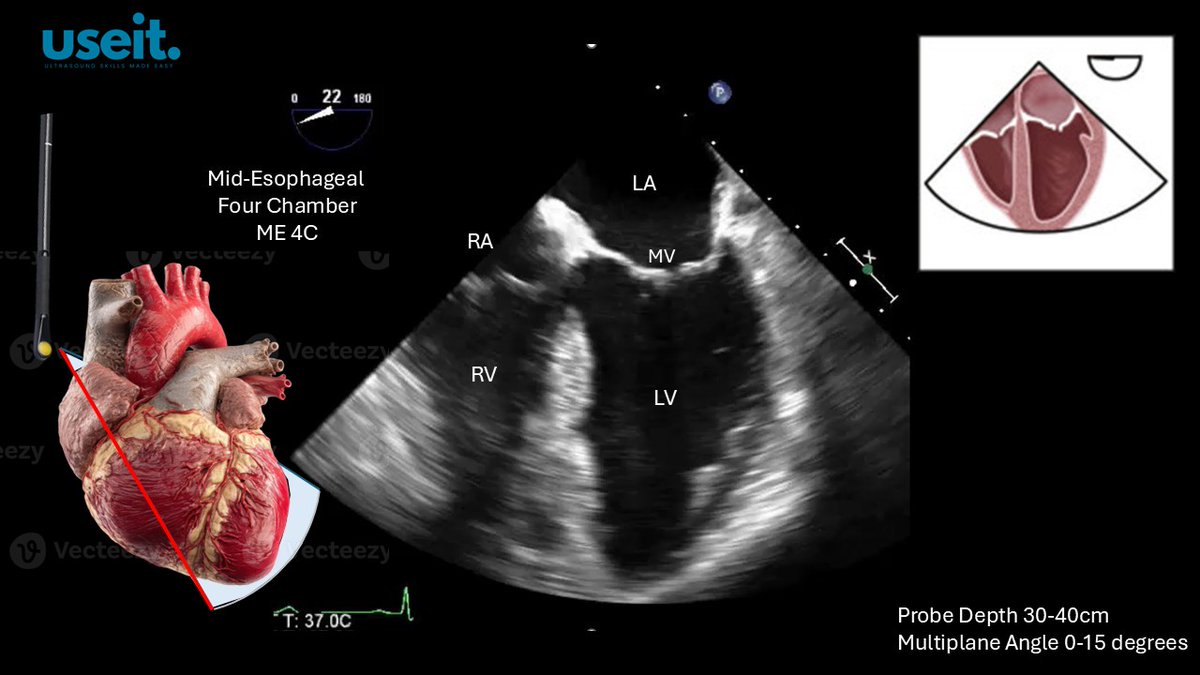

The ME4C view is obtained at a probe depth of between 30-40cm. The multiplane angle is set at between 0-15 degrees. All 4 cardiac chambers can be seen. The beam should pass throught the apex of the heart. #useit mobile app #TEE #POCUS

pocus_today's tweet image. The ME4C view is obtained at a probe depth of between 30-40cm. The multiplane angle is set at between 0-15 degrees. All 4 cardiac chambers can be seen. The beam should pass throught the apex of the heart.